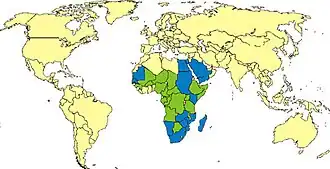

La fiebre del valle del Rift (RVF, por sus siglas en inglés) es una zoonosis viral que afecta principalmente a ganado doméstico, pero que puede infectar a seres humanos, causando fiebre. Se propaga por la picadura de mosquitos infectados. La enfermedad es causada por el virus de la fiebre del valle del Rift, un miembro del género Phlebovirus (familia Phenuiviridae). La enfermedad fue por primera vez documentada en ganado en Kenia alrededor de 1915, pero el virus no fue aislado hasta 1931. El brote infeccioso se extendió a lo largo de la África subsahariana. También se sucedieron brotes en otros lugares menos frecuentemente aunque algunas de manera severa, como en Egipto entre 1977 y 1978, donde tuvo como resultado varios millones de personas infectadas y miles de muertos durante la epidemia. En Kenia, en 1998, el virus segó la vida de más de 400 kenianos. En septiembre de 2000, un brote infeccioso fue confirmado en Arabia Saudí y en Yemen.